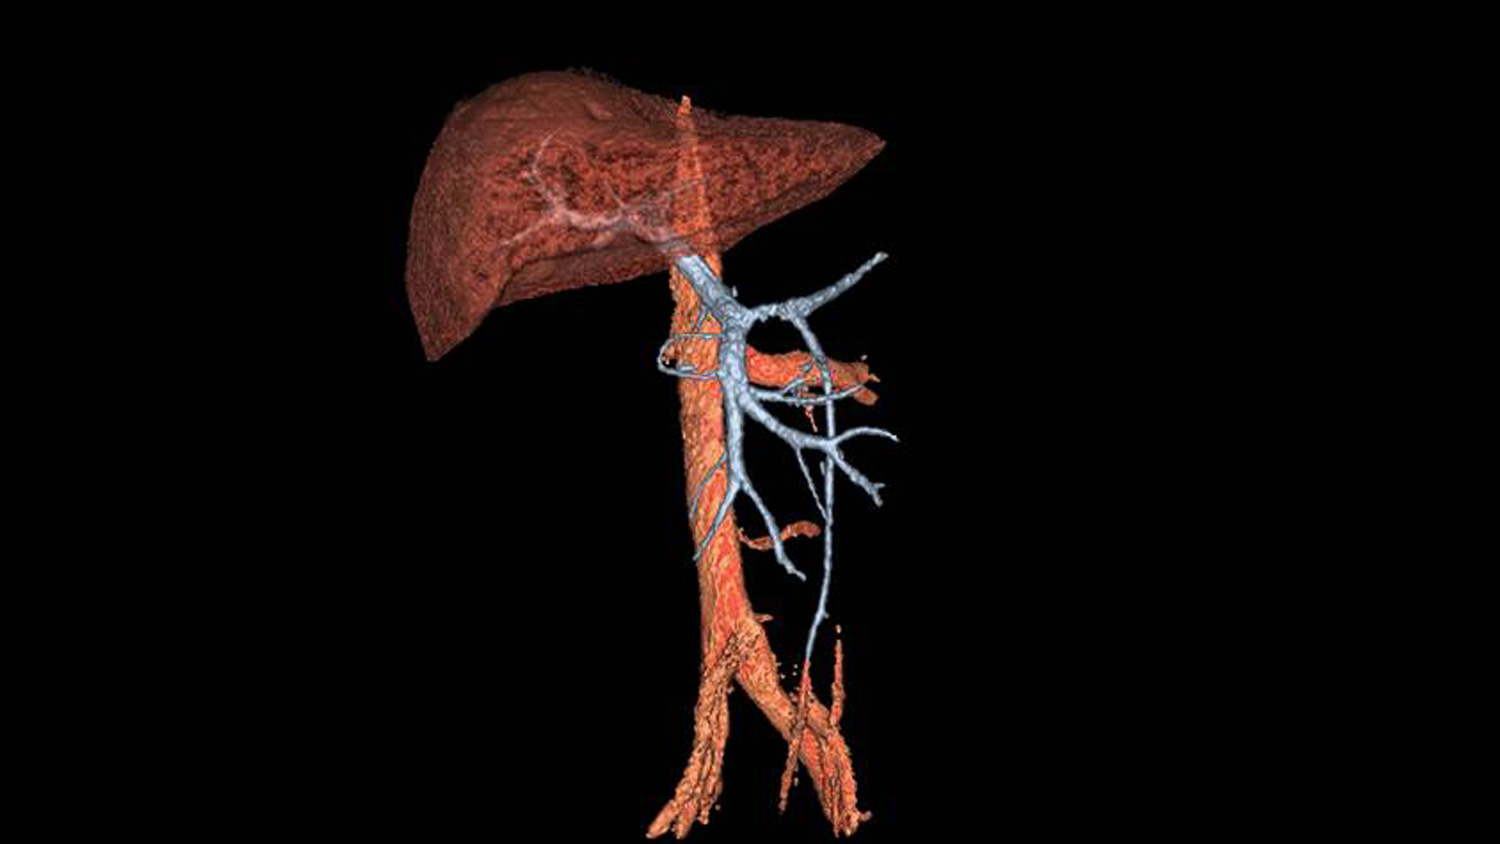

Ahora es posible realizar una angiografía a los pacientes con patologías renales sin necesidad de aplicar gadolinio y más importante sin sacrificar la calidad del estudio. La imagen es generada en alta definición (HD) y en reconstrucción 3D se puede ver a detalle de la anotomia renal del paciente. Con nuestra aplicación Inhance Suite 2.0 es posible visualizar el flujo arterial y venoso gracias a una avanzada gama de potentes y sólidas secuencias de pulso y sin necesidad de administrar contrastes de gadolinio.

Inhance es una técnica de angiografía sin realce de contraste por RM desarrollada para adquirir imágenes de las arterias y suprimir el tejido estacionario y el flujo venoso de fondo. Esta secuencia proporciona una excelente relación señal-ruido (SNR) y genera imágenes de sangre blanca. Se aplican pulsos selectivos de inversión sobre la región de interés para invertir el tejido arterial, venoso y estacionario. En el punto nulo de los tejidos de fondo, se aplica un pulso de excitación para generar la señal. El resultado neto es una imagen angiográfica con una excelente supresión de la señal de fondo y libre de contaminación venosa. La técnica selectiva de saturación espectral química (SPECIAL) le permite lograr una supresión uniforme de grasa, mientras que la compatibilidad con el gating respiratorio reduce los artefactos provocados por el movimiento respiratorio durante las exploraciones renales en respiración libre.

Nos permite adquirir imágenes angiográficas de las arterias cerebrales y renales con una excelente supresión de la señal de fondo en un reducido tiempo de exploración. Mediante la adquisición de imágenes volumétricas 3D de contraste de fase combinadas con imagen en paralelo, un eficaz muestreo del espacio k y la optimización de las secuencias de pulso, es capaz de registrar toda la anatomía neurovascular en aproximadamente cinco a seis minutos. Además, la supresión de la señal de fondo mejora gracias al diseño optimizado de la secuencia de pulso, lo que contribuye a una visualización detallada de las ramas de menor tamaño. La técnica de adquisición de señales sincronizada con el ciclo respiratorio (respiratory triggering) también es compatible con Inhance 3D Velocity, lo que permite llevar a cabo angiografías abdominales, especialmente de las arterias renales. El resultado es una productividad y calidad de imagen excepcionales.

“Inhance Inflow IR proporciona imágenes exquisitas de la vasculatura renal, capaces de mostrar con precisión los vasos accesorios más pequeños y distales imposibles de visualizar en las RM con realce de contraste. Es la técnica de RM que estábamos esperando”